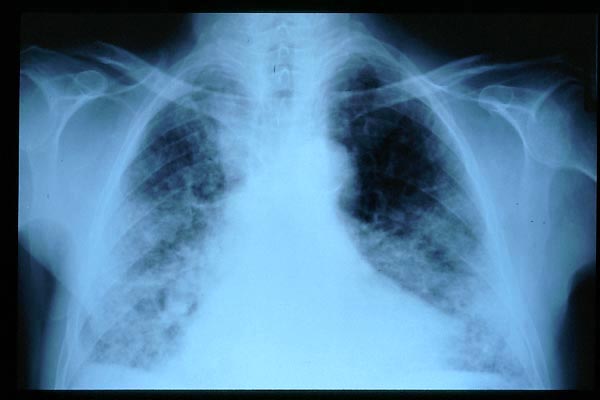

Fibrosis pulmonar. ICC.